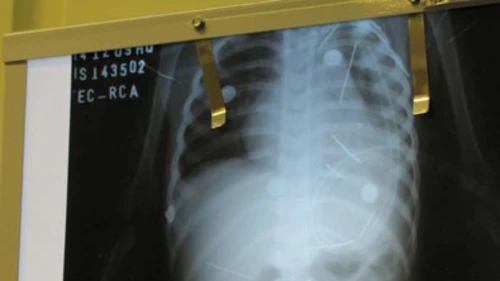

Un niño de dos años se encuentra internado en estado grave en Bahía, Brasil, luego de que los médicos detectaran, por medio de una radiografía, 50 agujas dentro de su cuerpo, que ya le perforaron un pulmón.

Las imágenes de las radiografías, divulgadas por varios periódicos en línea de Brasil,  muestran los pequeños objetos metálicos ubicados en el tórax, el abdomen, el cuello y las piernas del niño.